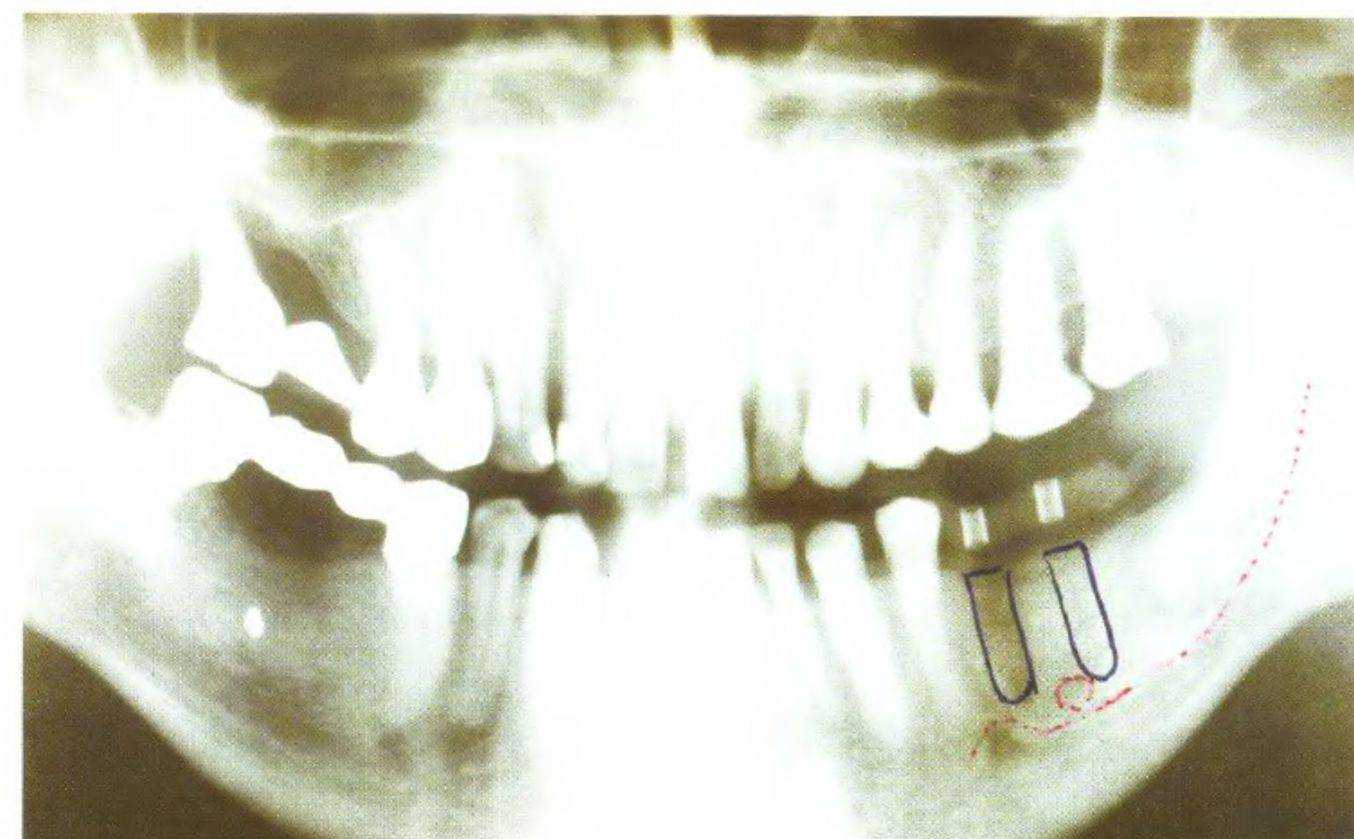

Высоту кости нижней челюсти можно определить с помощью панорамной рентгенограммы (рис. 3-41 с). Кроме того, панорамный снимок можно поместить в прозрачный файл и нарисовать на нем контуры имплантатов в нужном положении (рис. 3-42). Такой рисунок следует сохранить в карте пациента и использовать при получении информированного согласия на лечение. Затем следует провести калькуляцию приблизительной стоимости лечения. При получении согласия на общий план и стоимость можно приступать к более детальной диагностике (рис. 3-43 и 3-44).

При получении панорамной рентгенограммы совершенно необходимо использовать шарики или штифты для точного определения степени искажения в интересуемой области (рис. 3-52). Значительное усовершенствование панорамных рентгенаппаратов в последние годы позволило снизить степень искажения изображения и облучения пациентов. Производители имплантатов предлагают прозрачные шаблоны с изображенными на них имплантатами (все варианты длины и диаметра) с различной степенью увеличения, которую подбирают в зависимости от степени искажения рентгенограммы. Такие шаблоны накладывают на рентгенограмму для определения оптимальных по высоте участков (рис. 3-53а и 3-53Ь).

Обычно на панорамной рентгенограмме нижнечелюстные каналы и подбородочные отверстия визуализируются достаточно четко. Подбородочное отверстие всегда локализуется апикальнее второго премоляра. Таким образом, анализ панорамной рентгенограммы с помощью перечисленных выше инструментов позволяет определить высоту и ширину пространства для установки имплантата. Для изучения контура кости можно использовать остроконечный пародонтологический зонд, которым измеряют толщину мягких тканей в области предполага-

Современные панорамные рентгеновские аппараты позволяют делать не только панорамные снимки, но и томограммы. Искажение при получении томограмм (рис. 3-57 и 3-58) составляет 1:1,4, при использовании аппарата Сканора (Scanora)- 1:1,17. Ранее качество таких снимков оставляло желать лучшего, однако сегодня оно удовлетворяет диагностическим требованиям и продолжает повышаться (рис. 3-59а и 3-59Ь).